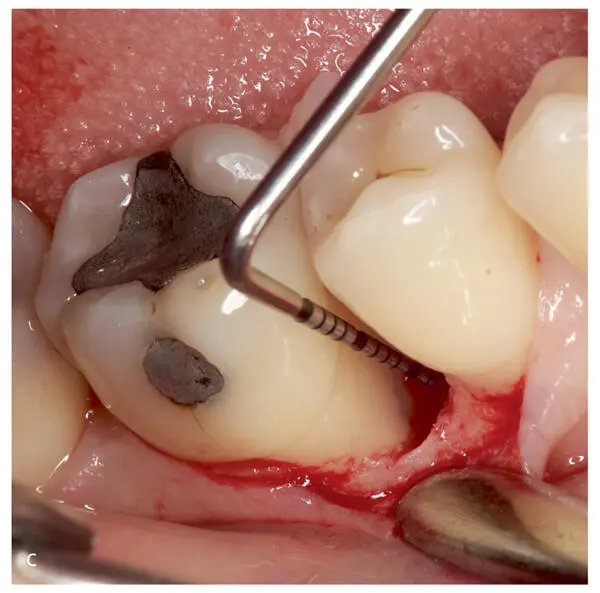

Figs 2-3a to cFor a complete periodontal examination, more precisely scaled periodontal probes are required. (a) The PCPUNC 15 explorer (pressure calibrated, diameter of 0.5 mm) represents the standard periodontal probe with a graduation of 1 mm steps. (b) To explore interradicular attachment loss, a bended periodontal probe (Nabers probe, 3 mm graduation) is recommended for determination of furcation involvement. (c) Presentation of the application of periodontal probes around molar teeth.

Figs 2-7a to eRepresentative images of the corrective therapeutic phase. (a) Intrabony three-wall defects subjected to regenerative periodontal therapy at maxillary right second premolar and first molar. (b) Wound closure upon application of enamel matrix derivatives onto the root surfaces. (c and d) Minimally invasive access to the three-wall intrabony defect at the mandibular right first molar. (e) Wound closure upon application of enamel matrix derivatives onto the root surface.